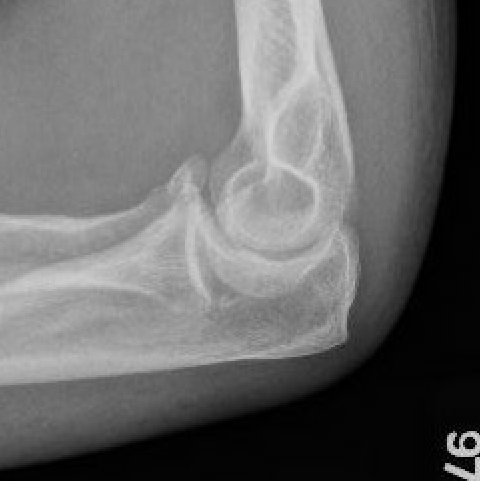

Coronoid Fracture Type 1 coronoid Type 3 Coronoid Fracture

coronoid coronoid coronoid